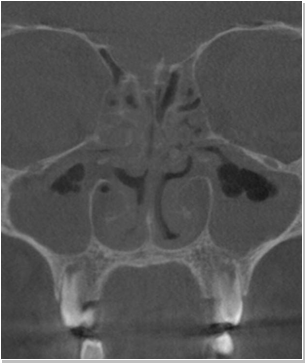

코재수술 CT 전후사진

비염

비중격만곡증

축농증